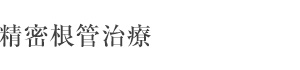

右下の奥歯が痛いとのことで来院された患者さん。

CTにて2次う蝕、根尖病変、根管が4本あることを確認し精密根管治療を行いました。

1年後のCTで病変が治癒していることが確認できます。